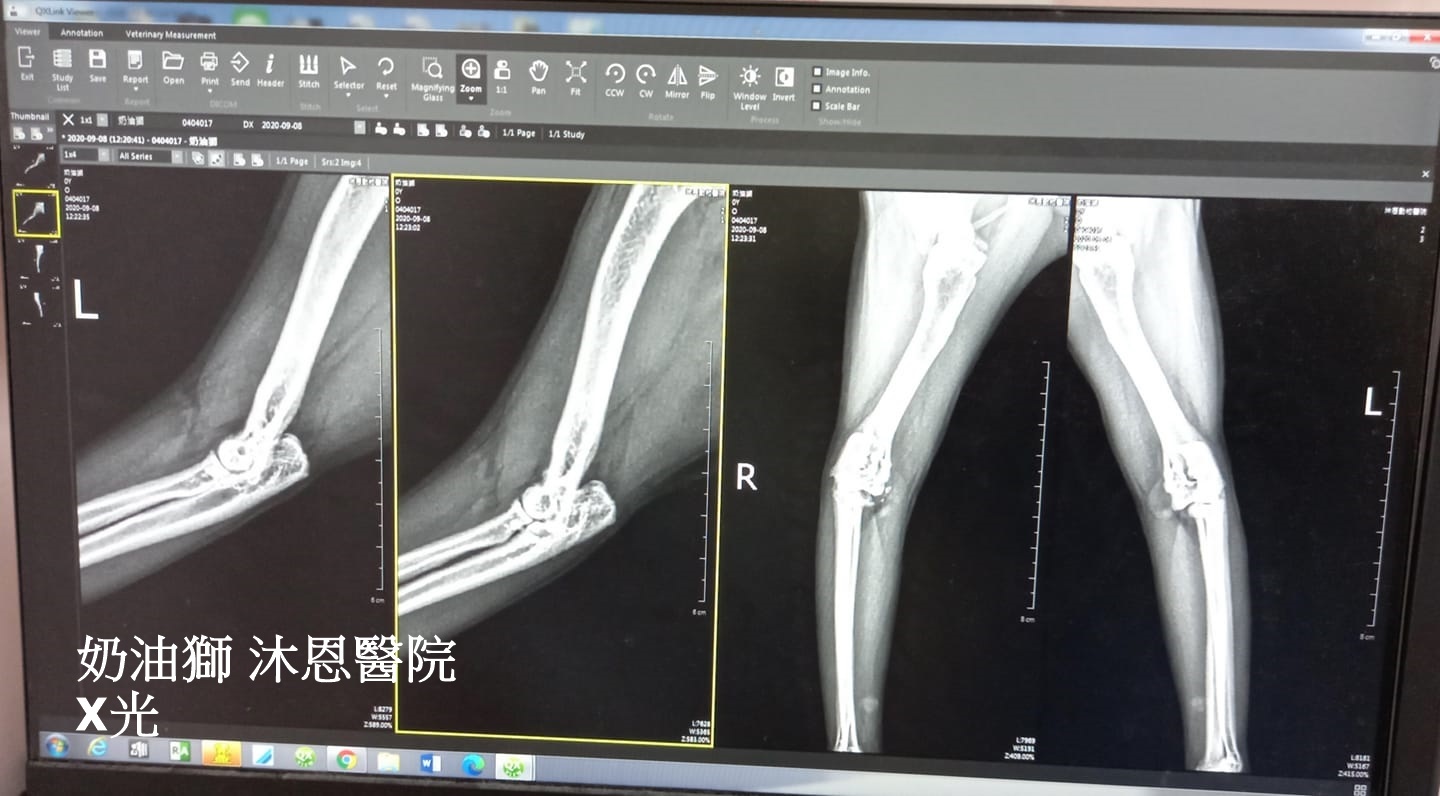

在9月初照護員發現奶油獅走路時前腳有些跛,約診沐恩檢查,經觸診及X光檢查是因退化及增生組織而造成的跛腳,除了是先天體質或有可能曾經發炎,建議是以吃保養品尋求改善也需控制體重以免增加腳步的負擔。

奶油獅走路時前腳有些跛,觸診檢查輕拉前肢,左手可配合醫師伸展,但右前手表現僵硬,X光檢查,左手沒異常,右手肘關節有退化及增生組織,因此在走路時會產生不適而跛腳。

林院長研判增生組織應是先天體質,或可能許久之前曾有過發炎所造成,但退化無法以手術處理,先吃關節保健品可以幫助修復,最主要的是須減重,只要體重減輕,疼痛跛腳情況就可以得到改善。